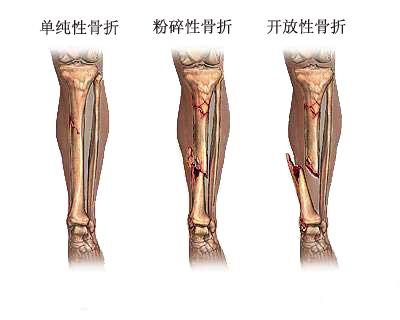

骨折损伤在生活中常意外出现,特别是在一些抗争性较强的体育项目中,尤为多发。

主要形式:加强患肢关节的主动运动,使各关节迅速恢复正常活动。下肢骨折病人可作上下坡、上下楼活动,在拐杖或手杖保护下,作一些负重的活动。骨折程度有轻重之分,重者多需要手术处理。但术后有些病患会出现肢体肿胀,十分难受。